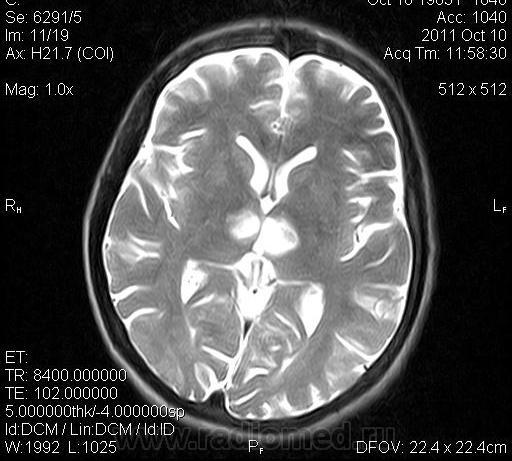

женщина 1963 года рождения. давность заболевания 10 дней.

ОНМК в бассейне правой и левой СМА (центральные ветви), подострый период.. Билатеральность нарушений может быть обусловлена вариантом строения Виллизиева круга.

Билатеральный таламический инфаркт. Либо венозный, либо вследствие закупорки одной из ветвей задней мозговой артерии - ЗМА (вариан развития ЗМА). Но не средней мозговой артерии (СМА). Мне представляеться, что здесь второе... За венозный инфаркт данных не вижу.

Я неприклонен... Инфаркт ЗМА (вероятно, варианта развития левой ЗМА - эмболии, мойа-мойа..).